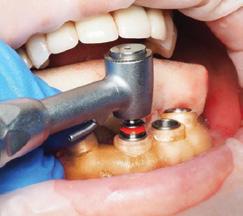

I am board certified in general and cardiothoracic surgery. Over the last few years I have refined my skills in minimally invasive surgery and most of the operations are performed robotically. Currently my scope of practice covers any chest pa thology including lung surgery, benign and malignant esophageal surgery among others surgeries in the chest.

Thoracic surgery is one of the most versatile specialties. I have particular interest in cutting edge technology such as robotic sur gery, navigational bronchoscopy and single incision surgery.

Lung surgery is the majority of my practice. I also perform surgeries in the esophagus; however, my scope of practice is very broad and in cludes surgery for reflux disease, thoracic outlet syndrome, surgery for diaphragmatic problems, chest wall reconstruction surgery and complex bronchoscopy and endoscopic procedures to mention few.

Medicine is an evolving field, you see so many innovations that can be overwhelming at times. In terms of surgery the technology with robotic surgery and minimally invasive techniques are very impres sive, however outside the OR we have seen the treatment of cancer change drastically. Radiation oncology, radiofrequency ablation and immunotherapy are just some of the innovations we see on regular basis.

Larry was referred to Dr. Luis Alberton, thoracic surgeon at Lo gan Health Medical Center. Dr. Alberton, one of the region’s most refined minimally invasive surgeons, assured Larry that robotic surgery would be the least invasive approach and would likely have a shorter recovery time. An avid outdoors man himself, Dr. Alberton understood the importance of a short recovery time for a person like Larry. Minimally invasive robotic surgery expedites a patient’s recovery time by avoid ing the chest wall trauma that would’ve been necessary for a more traditional thoracotomy.

In January 2022, three months after the bike accident, Dr. Alber ton performed a robotic lobectomy on Larry in which he removed about a quarter of his lung. Just two weeks after the procedure, Larry was able to resume some activities. And by the following summer, he was back biking Spencer Mountain. “I’m glad that I had somebody like Dr. Alberton taking care of me,” says Larry. “Tho racic surgery is a nice thing to have available in our community.”